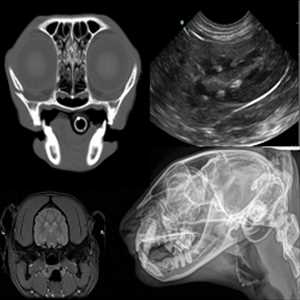

Mercado global Imágenes de diagnóstico veterinario por tipo:

Rayos X, Ultrasonido, MRI, Otros